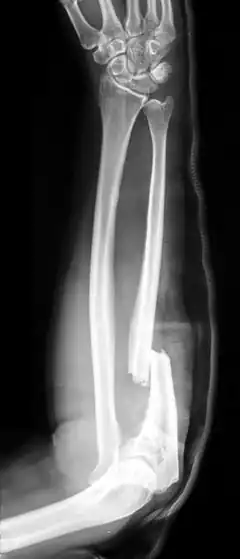

- Monteggia fracture - a fracture of the near to elbow end of the ulna with the dislocation of the head of the radius at the elbow joint.[2]

Monteggia Fracture (fracture of proximal ulna) -